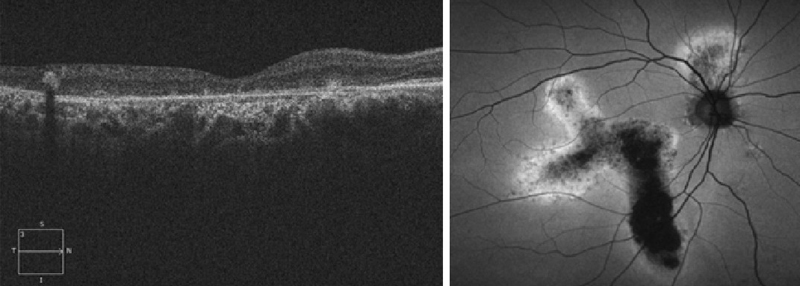

Otro subgrupo en el que puede objetivarse el cierre espontáneo es el de los agujeros maculares traumáticos. Según la serie estudiada

13,14, entre un 10% y un 40% de estas lesiones pueden cursar con cierre en los primeros 3 meses (

Figura 10), aunque en ocasiones este se acompaña de una atrofia de la retina secundaria al traumatismo. Los agujeros maculares traumáticos presentan unas particularidades respecto a los idiopáticos

15: suelen ser más delgados y no asocian signos de cronicidad (como edema quístico), son de base más ancha e irregulares, y en muchos casos persiste la adherencia de la hialoides posterior. Se han propuesto varios patrones por OCT sin que se hayan relacionado con pronóstico visual

16.

Figura 10. Cierre espontáneo de agujero macular traumático. Se aprecia en la retinografía el edema del polo posterior. En la tomografía inicial se objetivan las particularidades de estos agujeros: son más anchos en la base, no suelen asociar signos de cronicidad ni edema quístico y habitualmente son irregulares.